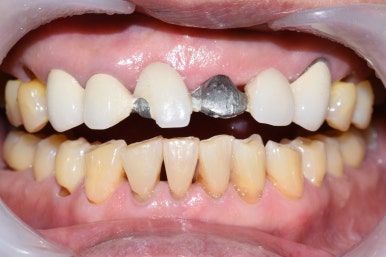

어차피 양 옆 치아도 많이 썩어있었기 때문에 임플란트 보다는 브릿지를 하기로 하였습니다.

이렇게 전 후 사진비교해보니

브릿지를 하고 훨씬 나아졌습니다.